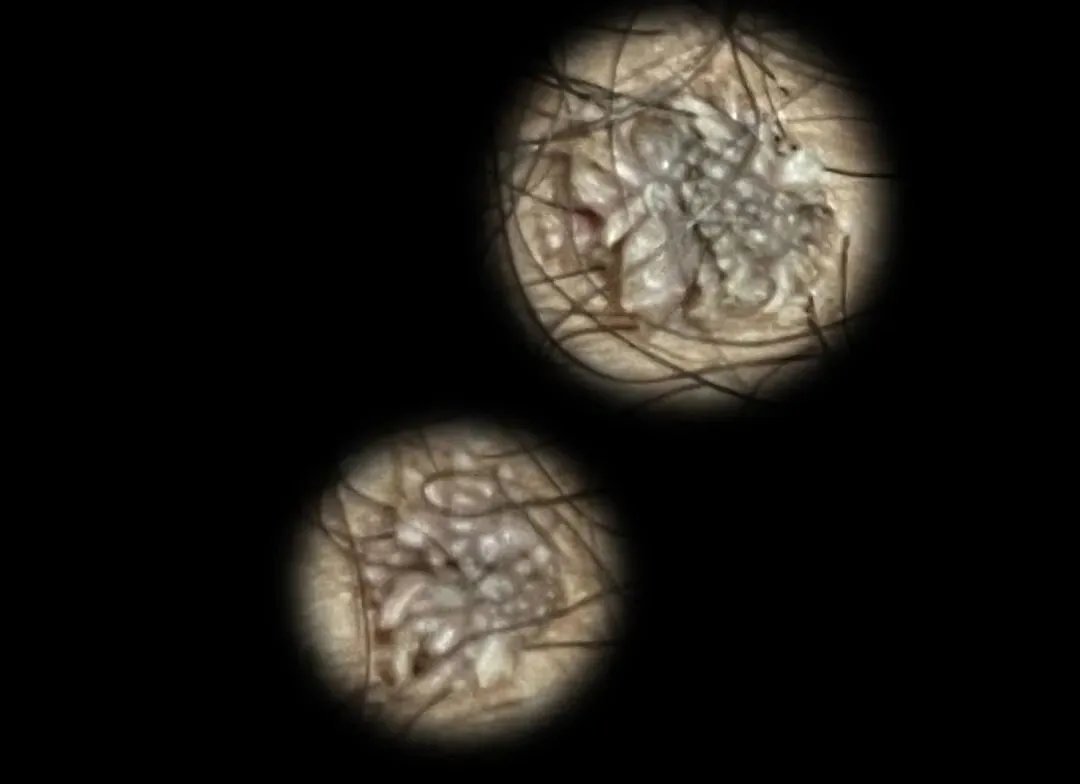

尖锐湿疣长什么样

尖锐湿疣是由人体人乳头瘤病毒(HPV)感染引起,常在肛门和外生殖器的皮肤黏膜赘生物。主要的症状就是生殖器部位、肛周和口腔等地方长菜花状、乳头状和鸡冠状的肉疙瘩,摸起来有很强的异物感,主要的症状图如下:

(此图为男性龟头疣体)

(此图为男性冠状沟疣体)